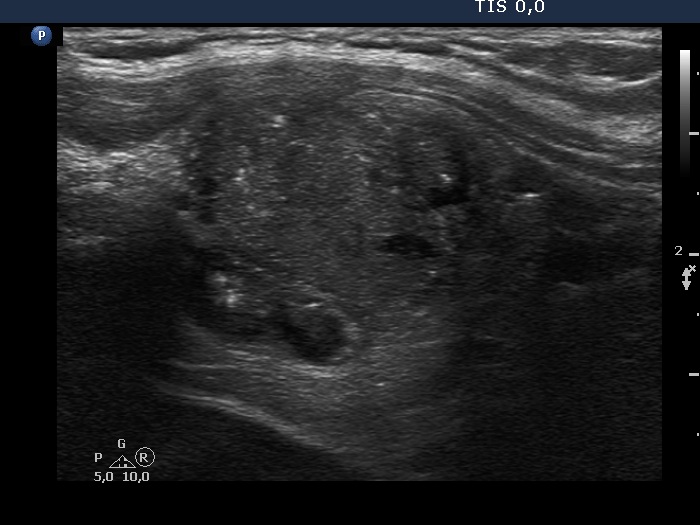

Ultrasonography. The presentation of the thyroid was essentially the same as 7 years ago. The only discrepancy was the lesion in the left lobe. Firstly, the size of the lesion have substantially increased to 25x18x25 mm (width, depth, and length, respectively), the volume was 5.89 mL which means that the volume became almost 8-times larger. Secondly, it was no more question whether the lesion was a pathological nodule or not. It turned out that this lesion is clearly a pathological nodule. Thirdly, in contrast to the former examination, the nodule has numerous microcalcifications and showed a clearly irregular, lobulated margins.

Comments:

We could not decide on the first ultrasound whether the lesion in the left lobe would be a nodule in a pathological sense. The presence of other similar areas decreased the possibility being the larger lesion a true nodule.

By reviewing the original smear, we found scattered numbers of grooves and two or three inclusions. It is difficult for a person to judge his or her own opinion, but it may well be that this pattern should not be judged as Bethesda III but as a suspicion of malignancy.